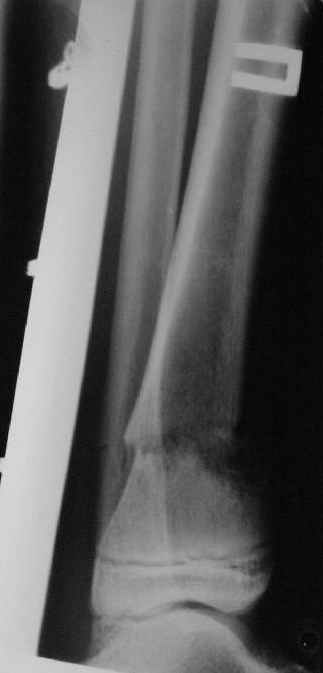

Промежуточный

|

Заживление проксимальной части раны вторичным натяжением без нагноения. Рана зажила. Спицы удалены через 1,5 недели после операции.

Учитывая фон (интеллект, etc) гипсовая повязка.

На данный момент ходит при помощи костыля (без присмотра -без костыля :), разрабатывает движения в г\стопном суставе.